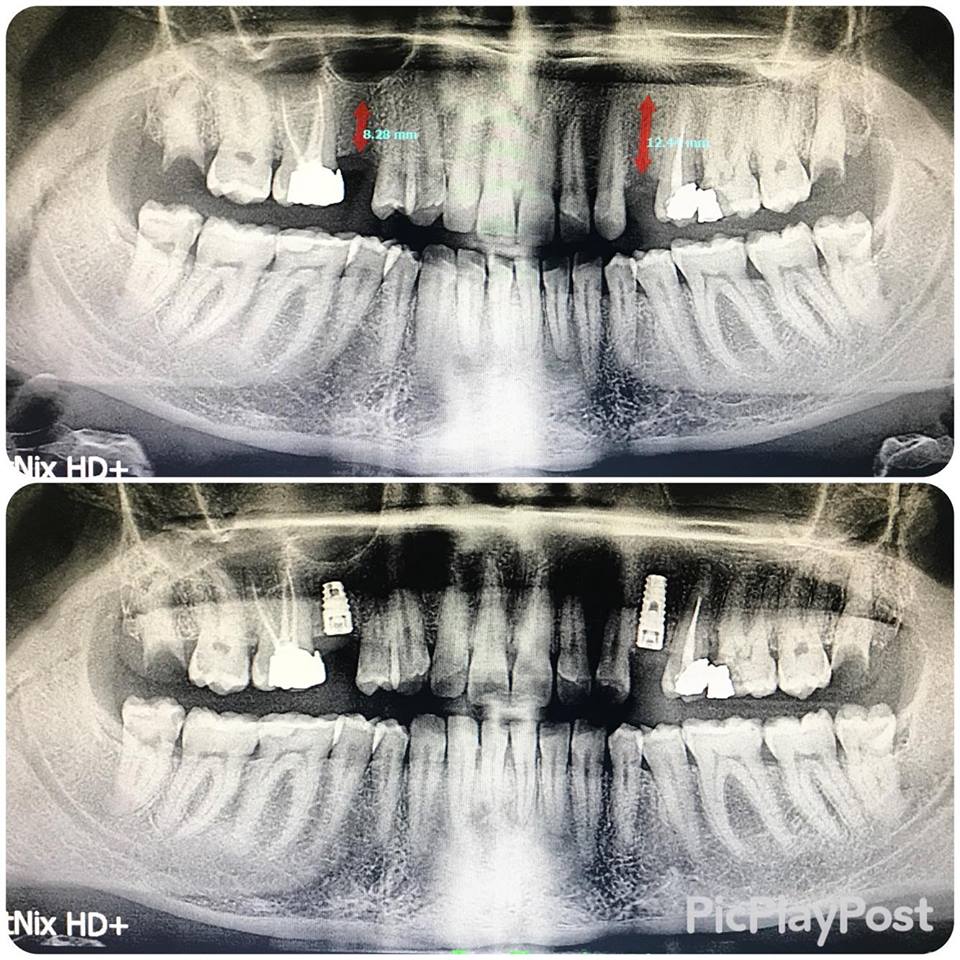

implant tedavisi